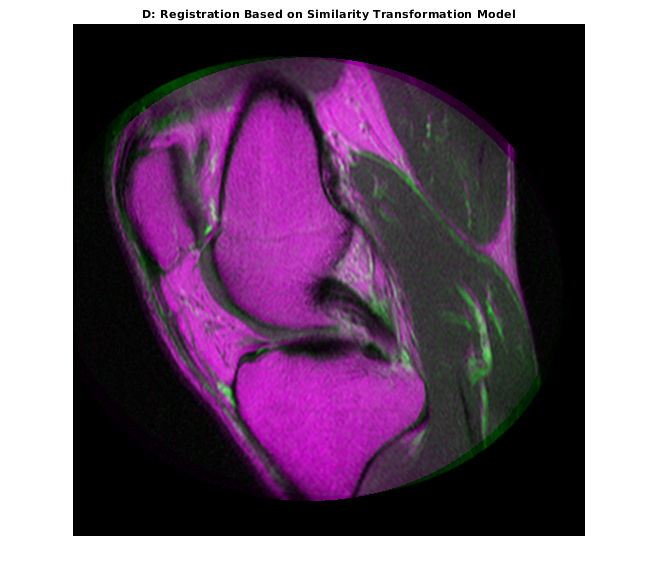

movingRegisteredRigid = imwarp(moving,tformSimilarity,'OutputView',Rfixed); imshowpair(movingRegisteredRigid, fixed) title('D: Registration Based on Similarity Transformation Model')

Свойство 'T' выходного геометрического преобразования задает матрицу преобразования, которая сопоставляет точки в перемещении в соответствующие точки в фиксированном.

tformSimilarity.T

ans = 3×3

1.0331 -0.1110 0

0.1110 1.0331 0

-51.1491 6.9891 1.0000